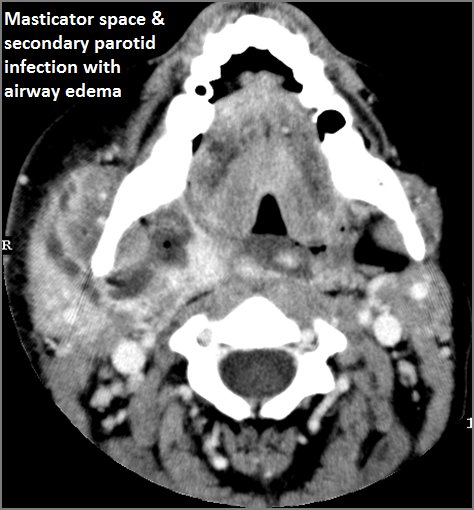

There is significant secondary airway encroachment present.

There is edema (cellulitis) and/or abscess within the fat surrounding the parotid gland and/or of the masticator space or other adjacent spaces.